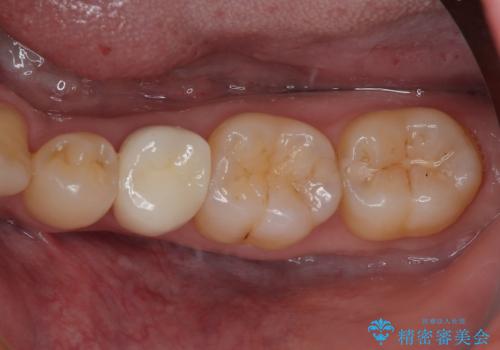

左下が虫歯になっている気がする オールセラミッククラウン

担当医 有澤哲郎